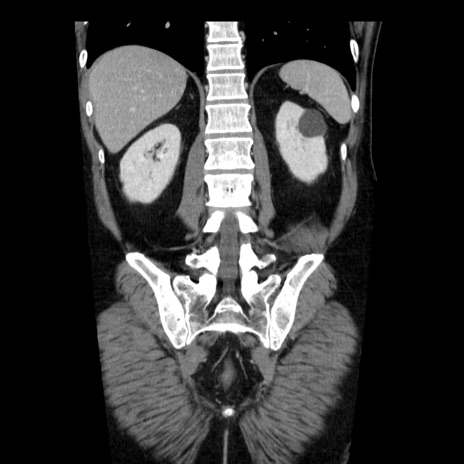

症例29(冠状断像)

【症例】40歳代男性

【現病歴】2日前から胃痛あり。徐々に周期的な激痛に変化した。本日になっても激痛があるため受診。

【身体所見】意識清明、BT 38-39℃台あり、腹部:膨満、やや硬、右下腹部に圧痛あり。

【データ】WBC 8500、CRP 23.26